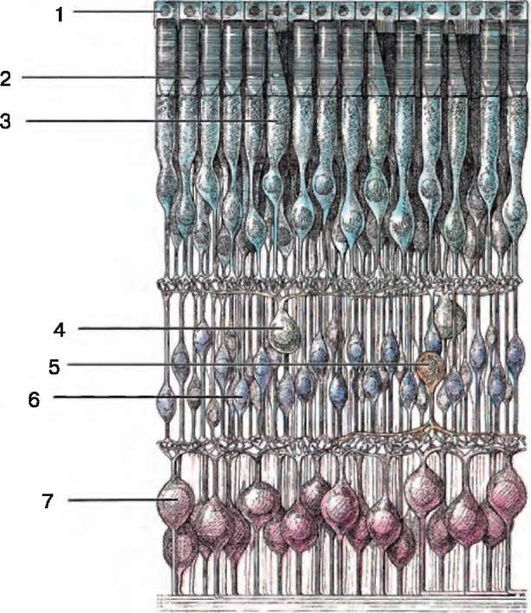

Рис. 1.3. Слои сетчатки (схема): I - пигментный эпителий; II - слой колбочек и палочек; III - наружная глиальная пограничная мембрана; IV - наружный зернистый слой; V - наружный сетчатый слой; VI - внутренний зернистый слой; VII - внутренний сетчатый слой; VIII - слой ганглиозных клеток; IX - слой нервных волокон; Х - внутренняя глиальная пограничная пластинка; XI - стекловидное тело